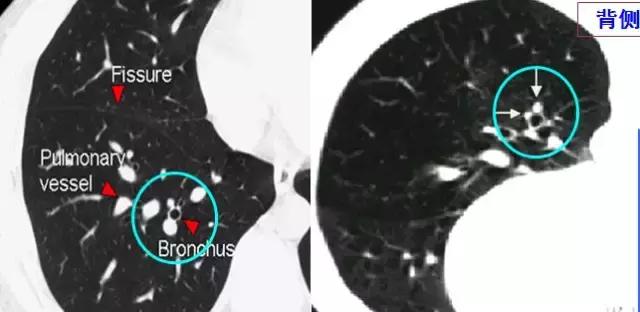

CT征象二:轨道征与印戒征

1、“轨道征”:扩张支气管走行与CT扫描平面平行时

2、“印戒征”:扩张支气管与CT扫描层面垂直时

(正常同级别的肺动脉直径稍大于伴行的支气管内径)

CT表现:在肺野内显示为平行的线样高密度影或环形低密度影伴周围点状高密度影(直径小于前者)

柱状支气管扩张与扫描层面垂直——“印戒征”